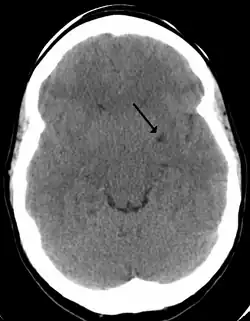

Son una estructuras fisiológicas en el parénquima cerebral normal.[2] Consisten en espacios perivasculares que rodean a las arterias perforantes del cerebro, y se debe pensar siempre en ellos al visualizar estructuras quísticas en la sustancia blanca del cerebro y ganglios basales, redondeadas o alargadas, siguiendo el trayecto de los vasos perforantes.[5]Se pueden observar a través de una resonancia magnética cerebral.[5] Allí las características morfológicas de imagen de los espacios de Virchow-Robin son áreas redondas o tubulares, de bordes suaves.[2]

En ocasiones pueden crecer y convertirse en gigantes espacios de Virchow-Robin.[4]Al agrandarse y convertirse en espacios gigantes de Virchow-Robin producen un efecto de masa que puede traer diversos síntomas neurológicos.[1]En casos anormales se relacionan con diversas patologías neurológicas neurodegenerativas, como la enfermedad de Alzheimer, las enfermedades cerebrovasculares y las lesiones cerebrales traumáticas,[2]ictus, esclerosis múltiple, angiopatía amiloidea cerebral,[6] e hidrocefalia.[3]Incluso se ha descrito un caso de neuralgia del trigémino secundaria a los espacios de Virchow-Robin gigantes en el área dorsal pontino.[1]